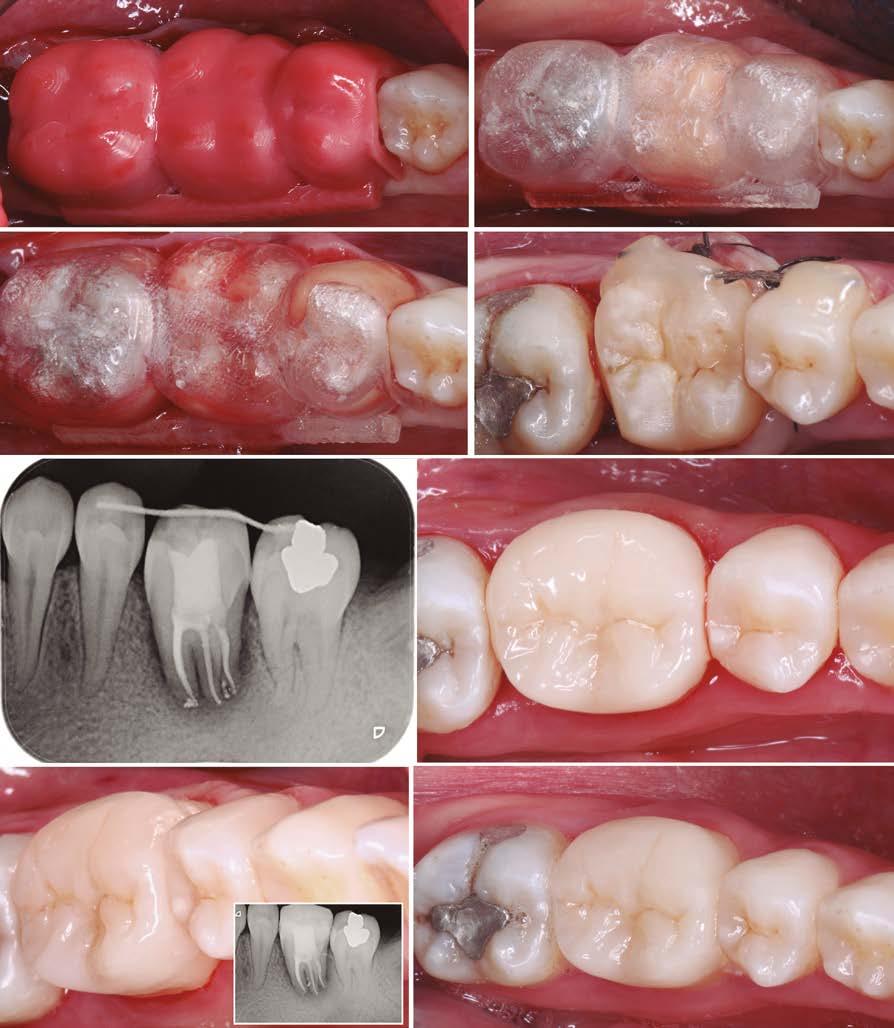

Presentación del caso clínico

A continuación, presentamos el caso clínico de una paciente con unos dientes mal posicionados y con una coloración acentuada sobre todo a nivel de los centrales que además presentaban extensas restauraciones antiguas de composite en interproximal cerrando diastemas que originalmente presentaba la paciente. Estos dientes necesitarán tener una preparación un poco más subgingival y también removido previamente todo el composite antiguo con el objetivo de camuflar este cambio de color y evitar zonas visiblemente no estéticas.

Además, lo combinaremos con unas carillas inyectadas inferiores también planificadas digitalmente y sin tallado, para crear una armonía y equilibrio con la parte superior.

Como podemos observar la paciente tenía un sustrato muy desfavorable, con un color aproximado de A3,5 Vita.

Para la arcada inferior se optó por unas carillas inyectadas, completamente respetuosas con los tejidos, que nos permiten mejorar la apariencia de los dientes y dar así una mayor armonía con la parte superior. Al ser también planificadas digitalmente aseguramos que lo que colocamos en boca sea una fiel reproducción del diseño previamente aceptado por el paciente y el profesional.

En la arcada superior por el contrario se decidió poner unas carillas de disilicato para poder cubrir las expectativas de la paciente y ajustar el color al que ella deseaba, bajando casi en 5 tonos el color final. Se planificaron preparaciones digitales conservadoras.

La tecnología digital permite lograr el equilibrio de espesores ideal para cada caso, así como un eje de inserción adecuado. Todo esto permite dar una garantía de longevidad a las restauraciones planificadas.

En este caso se realizó una preparación previa a la preparación guiada en los márgenes y zonas interproximales, para camuflar el sustrato y dar una correcta inserción; y posteriormente se utilizaron unas guías de tallado diseñadas digitalmente para obtener los resultados precisos y predecibles que requería el caso.

La preparación previa junto a la preparación guiada, resultaron en un equilibrio ideal para los espesores mínimos que requería el caso. Se realizó una prueba en seco para valorar el ajuste final de las restauraciones.

Para cementar las carillas y evitar movimientos no controlados y una incorrecta cementación, utilizaremos una guía de posicionamiento simultáneo, esta guía no es de cementación en bloque ya que las carillas están perfectamente individualizadas. Únicamente sirven para llevar a la boca del paciente las carillas y cementarlas de una forma 100% segura, evitando el estrés que genera un posible movimiento durante la cementación y acelerando los tiempos de trabajo.

Consiguiendo así una perfecta adaptación de los márgenes de las restauraciones y la sensación de naturalidad e integración que se observa en la imagen final.

Como se puede observar en la imagen comparativa, la planificación se reproduce de una forma fiel a lo que se había planificado y aceptado por la paciente. Por tanto, no es una técnica susceptible al operador, que se realiza controlando mucho mejor los tiempos y los resultados obtenidos.